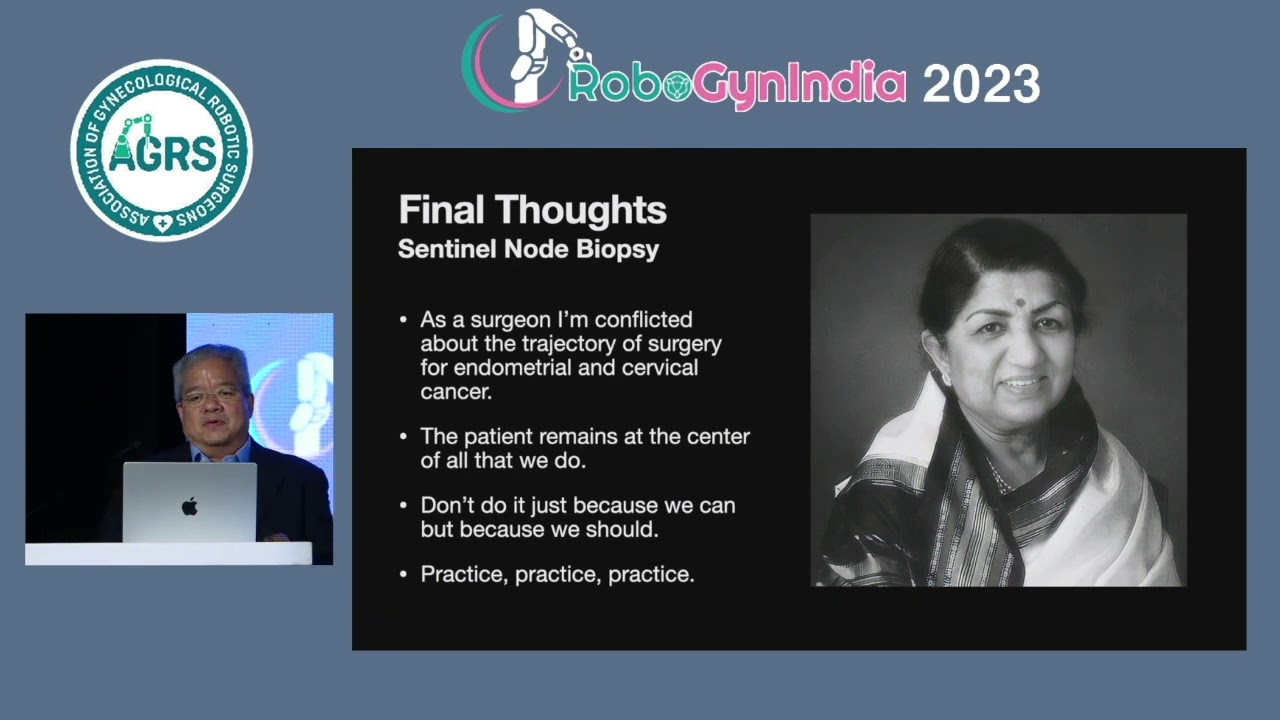

RoboGynIndia ’23 Day 1 Master Class 2 Robotic Hysterectomy for Cervical Cancer with Sentinel Node

Gynecology, Masterclass, Robotics, Surgeon ';